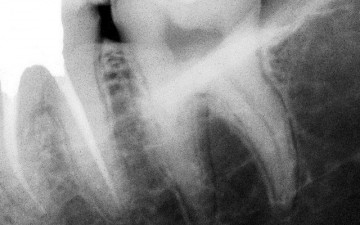

Pr K. BALTO, Saudi Arabia 1/3 Preoperative X-ray: tooth n°18 with irreversible pulpits and symptomatic apical periodontitis.